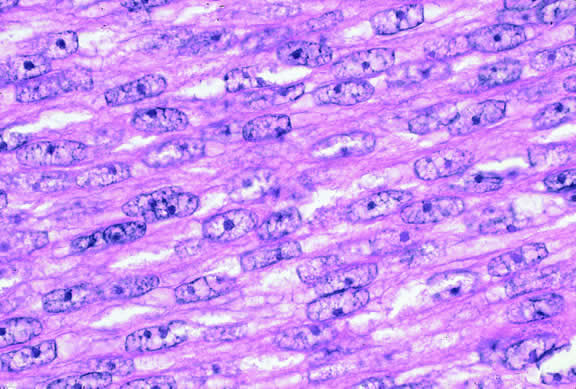

Histopathology

The cells comprising uveal melanoma constitute a biologic spectrum comprising bland spindle A melanoma cells at one end and wildly anaplastic epithelioid cells at the other. The term spindle cell is derived from the fusiform or spindled configuration of the cells' cytoplasmic outline. They are bipolar in shape, and many have long tapering processes that occasionally are highlighted when individual pigmented cells are seen in a largely amelanotic tumor. Spindle cells grow in a syncytial fashion forming interweaving fascicles of parallel oriented cells (Fig. 30). The cells can be pigmented or nonpigmented. Two types of spindle cells are recognized; spindle A and spindle B. These are distinguished by their nuclear characteristics. Spindle A nuclei are tapering ovals or cigar-shaped and have finely dispersed chromatin (Fig. 31). If a nucleolus is present, it usually is inconspicuous. Many spindle A cells have a longitudinally oriented chromatin stripe that actually is caused by a fold in the nuclear membrane. The nuclei of spindle B cells have distinct nucleoli and coarser chromatin and tend to be plumper and more oval in shape (Fig. 32).

Fig. 31. Low-grade spindle melanoma. Spindle A cells have bland, slender, cigar-shaped nuclei with finely dispersed chromatin and indistinct nucleoli. Longitudinal folds in the nuclear membrane are apparent microscopically as a chromatin stripe or line. Bland spindle B nuclei with distinct nucleoli also are present. (Hematoxylin-eosin, × 250.)

Fig. 32. Spindle B melanoma cells. Most of the cells in this field are spindle B melanoma cells. They have oval nuclei and an obvious nucleolus. Compared with spindle A cells, their chromatin is more coarsely clumped. The spindle cells form a syncytium and have indistinct cytoplasmic margins. (Hematoxylin-eosin, × 250.)

Epithelioid melanoma cells comprise the poorly differentiated end of the cytologic spectrum. Melanomas that contain epithelioid cells have a poorer prognosis. The term epithelioid meaning epithelial-like reflects the fanciful resemblance of the tumor cells to the cells of simple epithelia. Epithelioid cells have abundant cytoplasm and are often polygonal in shape (Fig. 33). They have distinct cytoplasmic margins, are poorly cohesive, and do not grow as a syncytium. The nuclei of epithelioid cells are usually round or oval and often appear vesicular because of margination or clumping of the chromatin along the inner side of the nuclear membrane. Epithelioid melanoma cells also have prominent nucleoli that are often large and reddish purple. Variants of epithelioid cells include relatively uniform small epithelioid cells (Fig. 34) and bizarre tumor giant cells that may appear wildly anaplastic (Fig. 35).

Fig. 33. Epithelioid melanoma cells. The cytoplasmic margins of these large, poorly cohesive epithelioid melanoma cells are easily discernible. Epithelioid cell nuclei are typically round and have peripheral margination of coarsely clumped chromatin. Epithelioid cells usually have prominent reddish purple nucleoli. They typically are polyhedral in shape and have copious amounts of cytoplasm. (Hematoxylin-eosin, × 250.)

Melanoma cells should be classified by their nuclear characteristics. Spindle-shaped cells that have epithelioid nuclei occasionally are encountered; such cells are classified as epithelioid. In recent years, the term intermediate cell has been used increasingly. Intermediate cells are cells that have nuclear characteristics that are intermediate between spindle B and epithelioid. For example, one might apply the term intermediate cell to a spindle B cell that has a nucleus that is somewhat large and has a fairly prominent nucleolus.

Melanocytic tumors of the uvea are classified into four groups on the basis of cytology. Tumors composed entirely of spindle A cells or even blander nevus cells are classified as spindle cell nevi. Tumors composed of a mixture of malignant spindle A and spindle B cells are called spindle melanomas. Melanomas of mixed cell type contain a mixture of spindle and epithelioid melanoma cells (Fig. 42). Some laboratories specify the predominant cell type found in a mixed cell melanoma, for example, reporting mixed cell, predominantly spindle if only a few epithelioid cells are present. Epithelioid melanomas are composed predominantly of epithelioid cells. They are relatively rare and have the poorest prognosis. Most medium- and large-sized melanomas contain a mixture of spindle and epithelioid cells. In the COMS histopathology study, 86% of the posterior melanomas were classified as mixed cell type, 8% were of spindle cell type, and 5% were epithelioid.84 The association between cytology and mortality is known as the Callender classification.90 (See later section on prognostic factors.)

Fig. 42. Uveal melanoma, mixed cell type. Mixed cell melanomas are composed of a mixture and spindle and epithelioid cells. (Hematoxylin-eosin, × 250.)